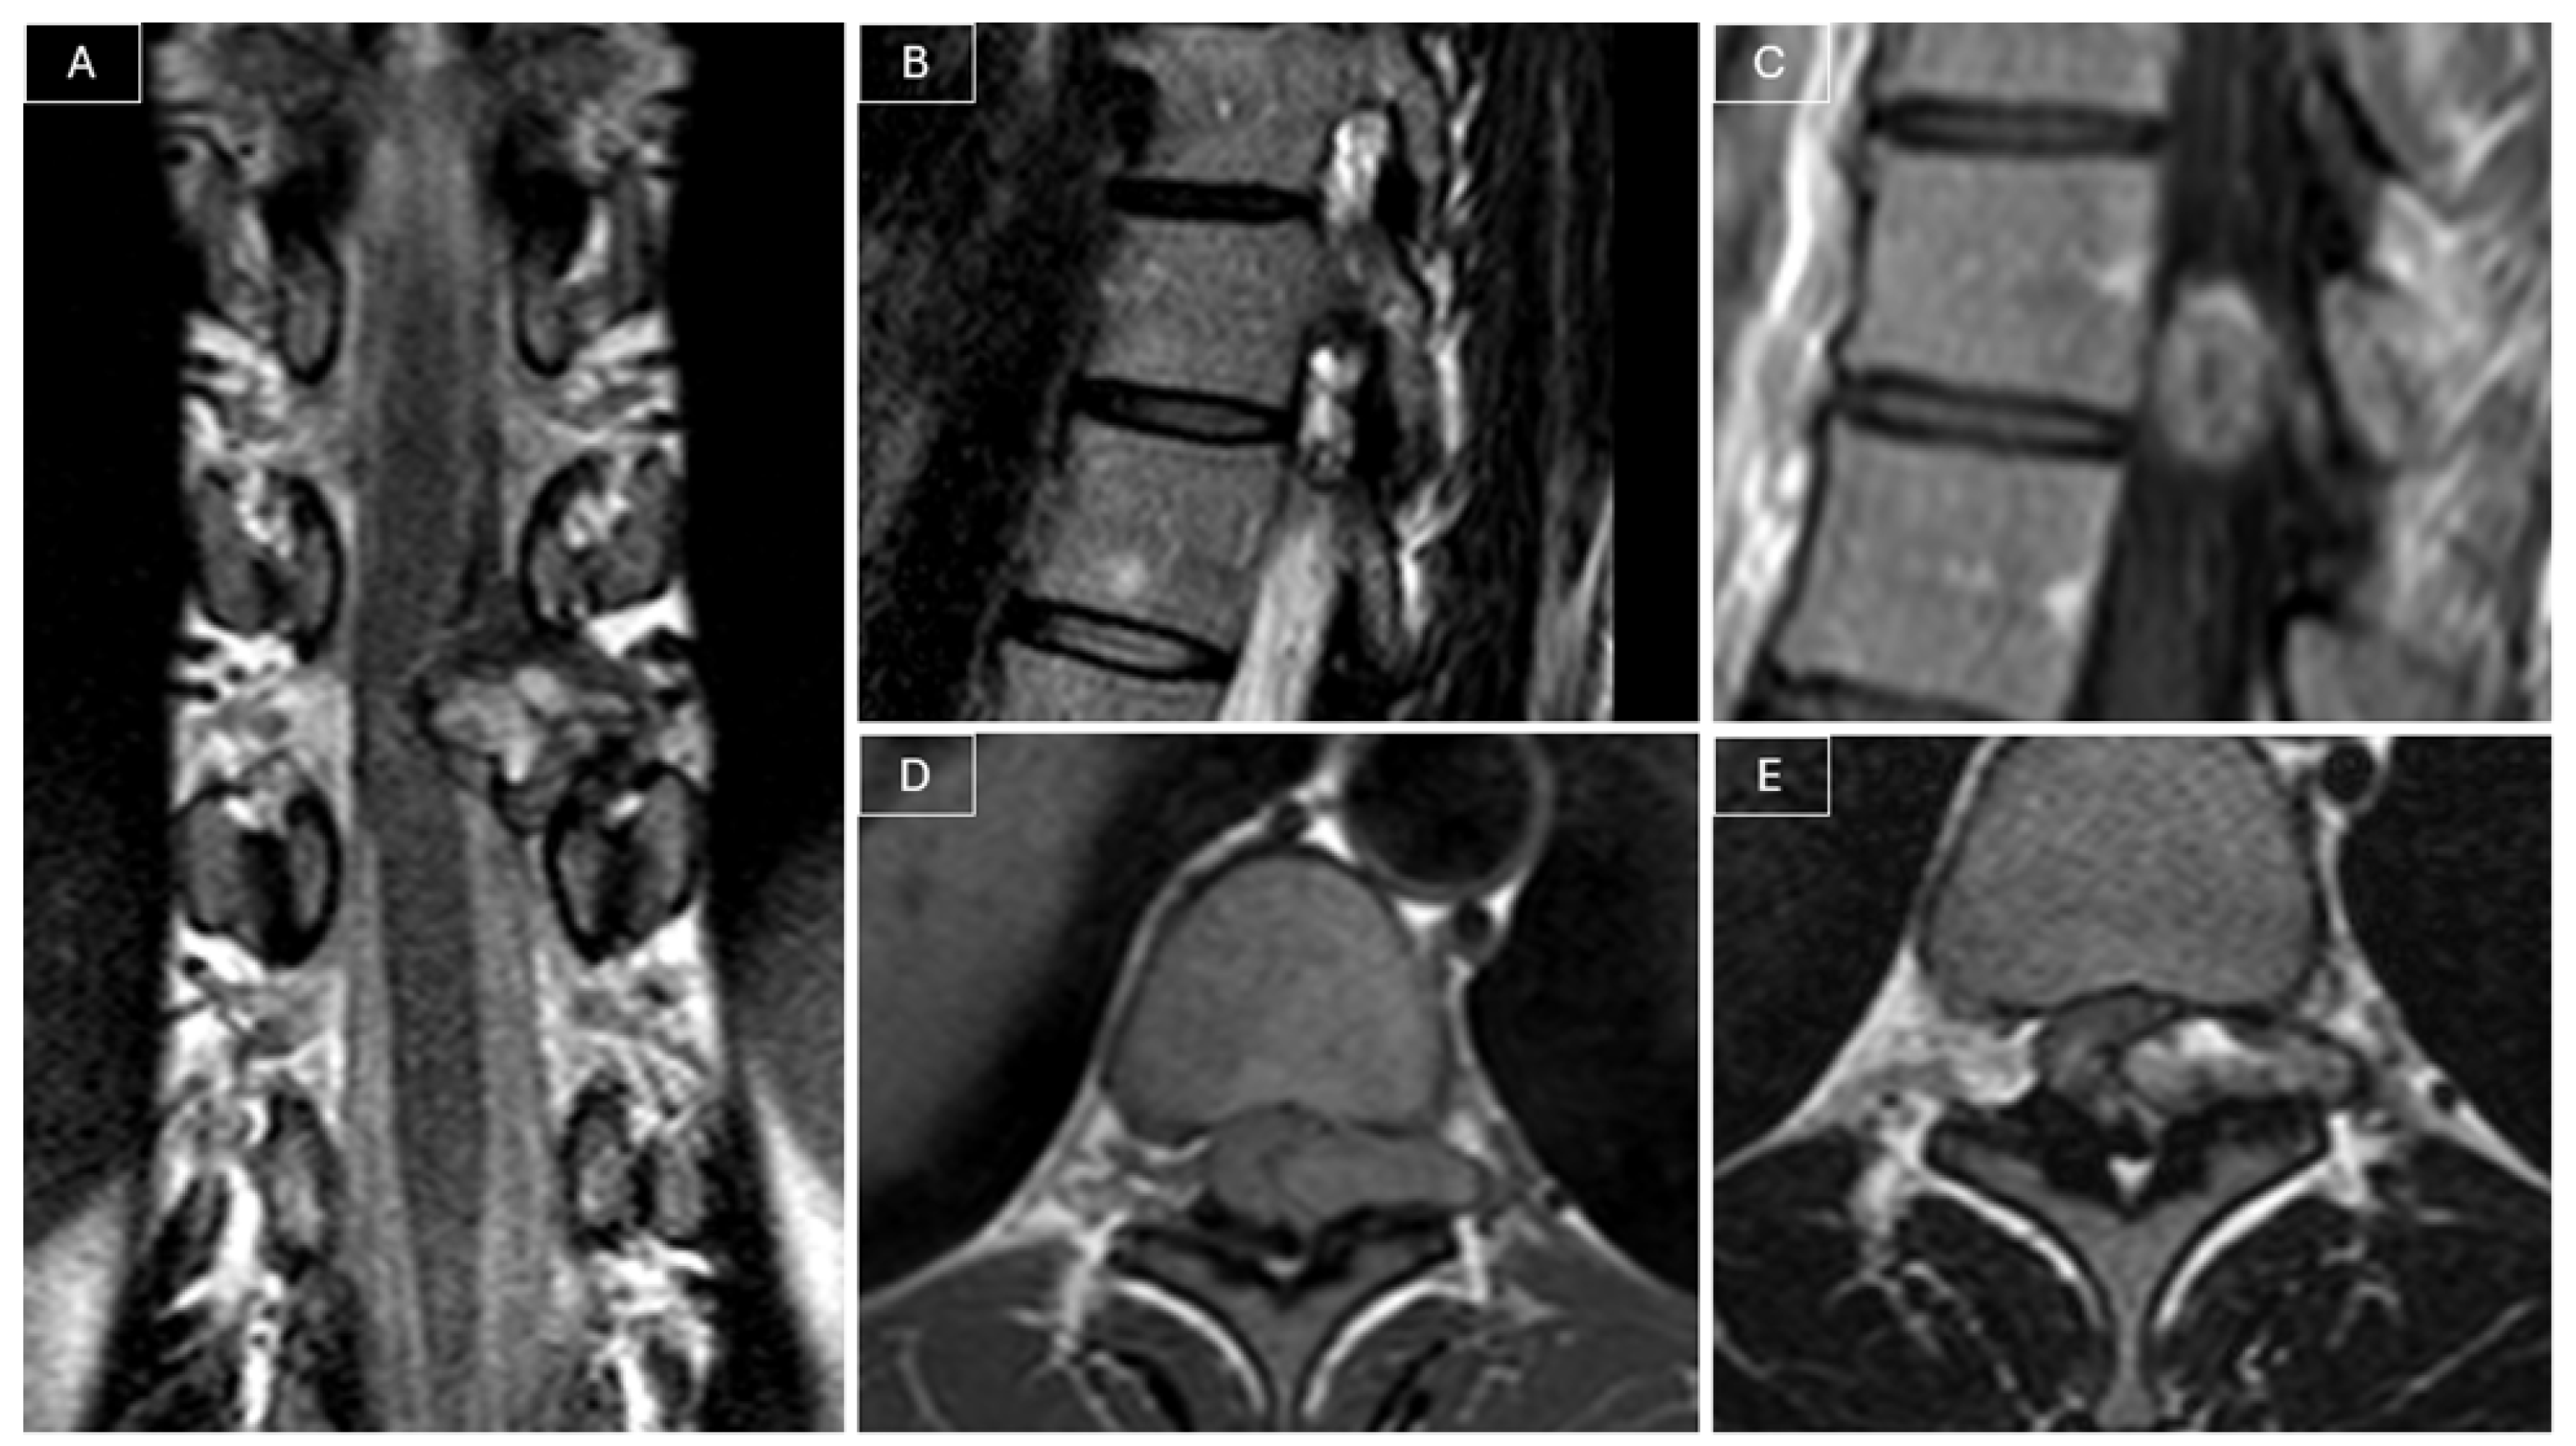

Magnetic resonance imaging (MRI) of the spine revealed a heterogeneously contrast-enhancing intra- and extracanalicular mass involving the left T10–T11 neural foramen. The lesion measured 21 × 8 × 21 mm and exhibited isointense signal on T1-weighted images and mildly hyperintense signal on T2-weighted images. The mass demonstrated both extradural and intradural components, compressing the spinal cord, and was initially considered a possible nerve sheath tumor given its location and partial extension into the neural foramen. (see Figure 1).

Figure 1. Preoperative MRI. (A) Coronal T2-weighted images demonstrated a heterogeneously hyperintense lesion compressing the spinal cord. The lesion appeared to have both intradural and extradural components and extended into the left T10–T11 neural foramen. (B) Sagittal T2-weighted images confirmed involvement of the left T10–T11 foramen by the tumor. (C) Sagittal post-contrast T1-weighted images showed the heterogeneous contrast enhancement of the lesion. The lesion appeared isointense on T1-weighted images (D) and slightly hyperintense on T2-weighted images (E).